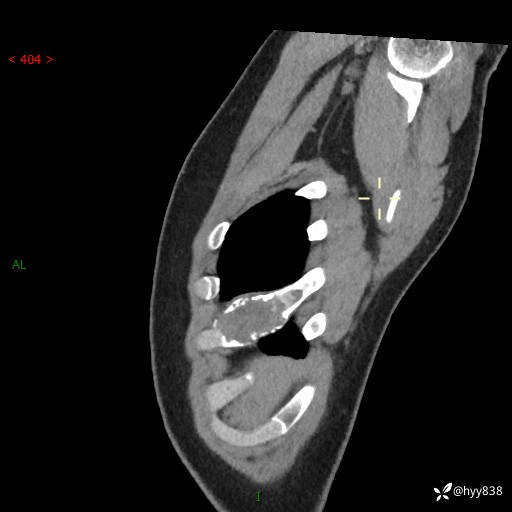

年轻小伙,右侧胸部疼痛4天余。病理科说肯定不是骨纤,那是啥---结果公布~

年龄:24岁

主诉:右侧胸部疼痛4天余。

现病史:患者约4天前突发右侧胸部疼痛,无瘙痒,无头痛、头晕,无心慌、胸闷、呼吸困难、咳嗽、咳痰、咯血,无腹痛、腹胀等不适,未作进一步诊治。于2024年5月外院行胸部CT平扫示右侧肋骨骨质改变。现为求进一步治疗,遂于我院就诊。门诊以“胸壁肿物”收入我科。 患者自起病以来,精神可,睡眠可,饮食可,大小便正常,体重无明显改变。

胸部CT平扫